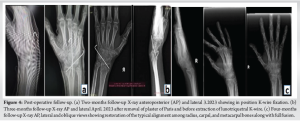

Following surgery, a defined period of immobilization through a POP cast was implemented for 3 months. This post-operative immobilization was intended to facilitate healing and promote successful fusion between the lunate and triquetral bones. The outcome of the surgical procedure exhibited successful fusion, as indicated by X-ray assessments demonstrating osseous integration and consolidation (Fig. 4). Once the cast was removed, a physiotherapy treatment plan was initiated promptly to regain mobility, enhance the ROM in the joint, and restore optimal hand functionality [5,8].

Subsequent clinical evaluations revealed progressive symptom improvement and enhanced wrist joint functionality, including reduced pain levels and increased ROM. The integration of the lunate and triquetral bones contributed to enhanced wrist stability and biomechanical function. Below, in Fig. 4, are successive X-ray images captured at the 2, 3, and 4-month follow-up intervals, depicting improved bone alignment and the gradual progression of fusion healing as time elapsed [9].

Alongside the X-ray images, presented in (Fig. 5 and 6), are photographs captured during a 6-month follow-up of the clinical case. These visuals showcase enhanced hand functionality, encompassing improved grip strength and expanded ROM in both wrist flexion and extension [3,6].